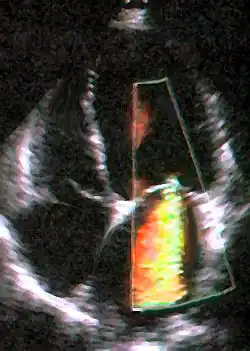

Transesophageal echocardiogram of mitral valve prolapse

Animation of a mitral valve regurgitation in a dog, left apical view

An echocardiogram is commonly used to confirm the diagnosis of MR.[16] Color doppler flow on the transthoracic echocardiogram (TTE) will reveal a jet of blood flowing from the left ventricle into the left atrium during ventricular systole. Also, it may detect a dilated left atrium and ventricle and decreased left ventricular function.[6] A transesophageal echocardiogram can give clearer images if needed as the back of the heart can also be viewed.[17]